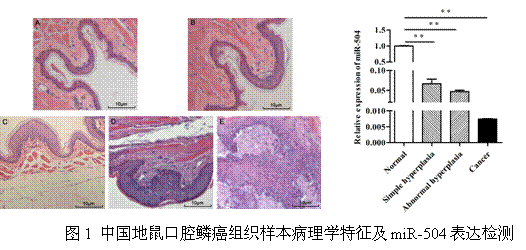

1 OSCC动物样本的病理特征及miR-504表达检测

根据中国地鼠口腔鳞状细胞癌动物模型组织样本的病理学特征将肿瘤的癌变分为四个阶段:药物诱导不同时间后中国地鼠的颊囊组织由正常上皮逐渐变为单纯增生的上皮组织,再到异常增生的上皮组织,并最终演变为口腔鳞状细胞癌(原位癌)。在不同病变阶段的动物组织样本中miR-504的表达随着肿瘤的不断恶化逐渐降低(图1)。